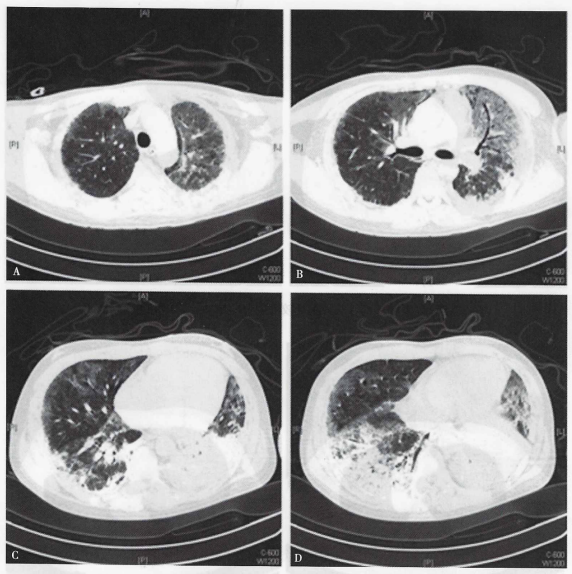

经与家属沟通,在目前治疗不变的情况下,1月7日加用环磷酰胺0.8 g静脉滴注。患者于1月9日出现幻视、眩晕等不适,考虑患者血G试验高,大剂量激素及环磷酰胺免疫抑制治疗,患者仍主诉黄痰,不宜停用抗真菌治疗,停用伏立康唑改为卡泊芬净治疗。治疗1周后患者体温峰值波动在37.5℃以下,1月10日激素减量至120 mg/d,幻视、头晕等症状明显好转,患者可下地绕床活动。1月17日再次复查胸部CT:双肺病灶较前明显吸收,纤维化较前明显好转(图3),当日将静脉滴注激素改为泼尼松80 mg/d分次口服,并停用莫西沙星。

图3  复查胸部CT提示两肺病灶较前明显吸收,纤维化较前明显好转